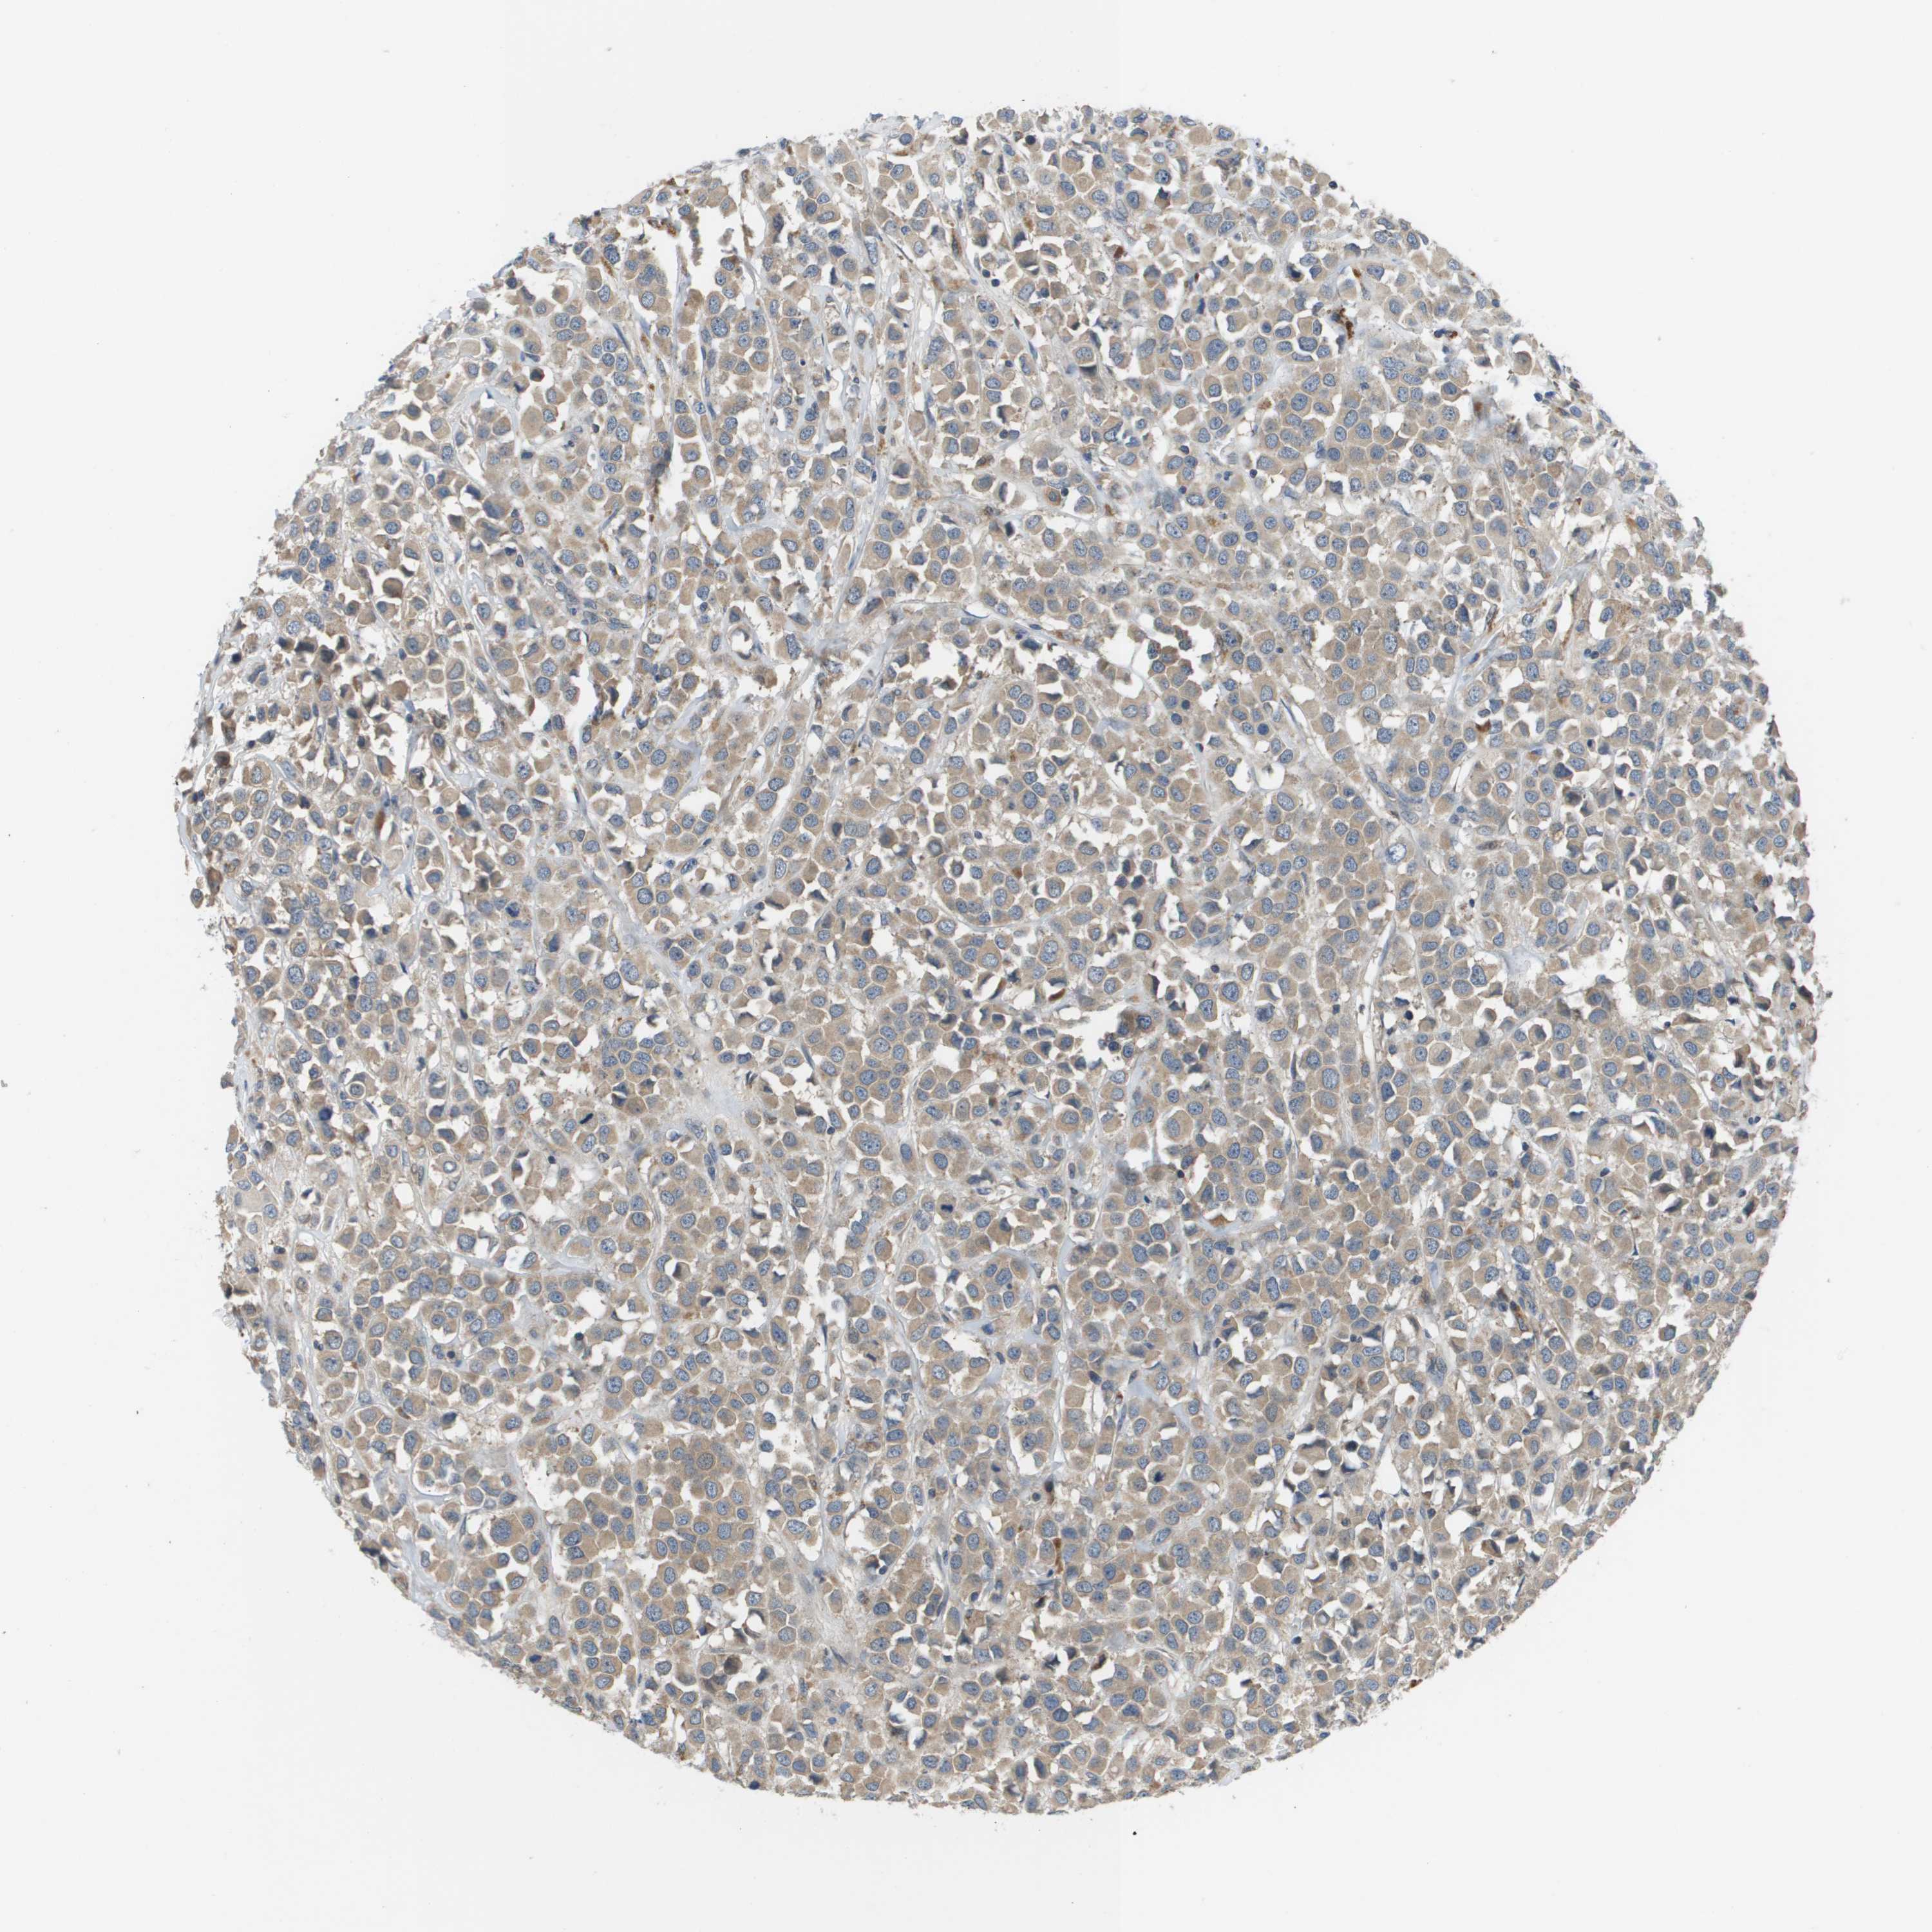

CANCER BREAST CANCER Show tissue menu

BRCA TCGA BRCA VALIDATION PROTEIN EXPRESSION